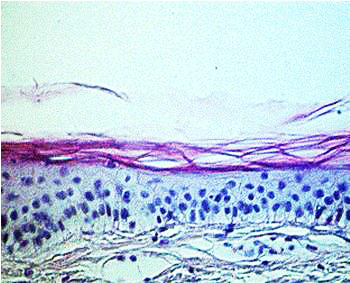

The in vitro skin models open up new opportunities for avoiding all these inadequacies. By successively culturing a dermis from fibroblasts and an epidermis with stratum corneum from keratinocytes, a skin-equivalent model (Fig. 4) can be created within 5 weeks, containing all of the main skin layers (7) (Fig. 5).

Fig. 5a

Fig. 5b

Fig. 5 a and b: Histological comparison of skin-equivalent model and normal human skin

After it has been cultured, the skin-equivalent model lives for at least another 4 weeks, during which time it remains virtually unchanged. During this time ageing experiments can be carried out, e.g., with UV irradiation or ozone, or tests of topical skin-protection or skin-care treatments. The main advantage is that, just like normal human skin, these skin models have a stratum corneum. The active substances can therefore be applied under realistic conditions in a cream or gel basis. The active substances penetrate through the stratum corneum into the skin, where they take effect.